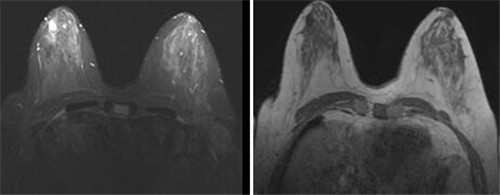

这是医院检查首例乳腺MRI,分别通过T1、T2、动态增强及TIC图对病变进行分析,诊断该病患右侧乳腺于乳头后上方病变为良性肿瘤,术后病理证实为纤维腺瘤。